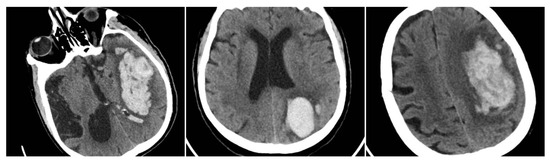

The Black Hole Sign (BHS) refers to a discrete, well-defined hypoattenuating region fully enclosed within a hyperdense clot with ≥28 HU difference and no continuity with normal parenchyma (BHS = 1 if present, otherwise 0) (Figure 2) [10].

Figure 2. Black Hole Sign (BHS)—three examples from our cohort.